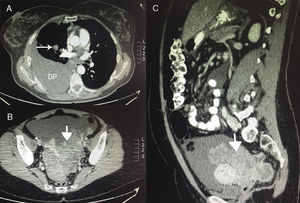

TAC del tumor de Krukenberg. A) Corte axial de la TAC a nivel del tórax donde se observa el derrame pleural (DP) derecho y un nódulo pulmonar parahiliar derecho. B) Corte axial de la TAC a nivel de pelvis donde se observa la masa pélvica. C) Corte sagital de la TAC donde se visualiza la masa pélvica.

En la TAC toraco-abdomino-pélvica (fig. 1) se objetivó una masa sólida y heterogénea de 13,7×8×5,4cm en la cavidad pélvica, que rechazaba útero y recto, compatible con una neoformación ovárica, además del derrame pleural, 3 nódulos pulmonares y otros en la grasa paracardiaca derecha, ascitis e implantes nodulares compatibles con carcinomatosis peritoneal, afectación metastásica en 3 arcos costales derechos y otra lesión hepática compatible con metástasis. El diagnóstico de presunción radiológico era de una neoplasia de ovario con diseminación abdominal y torácica.